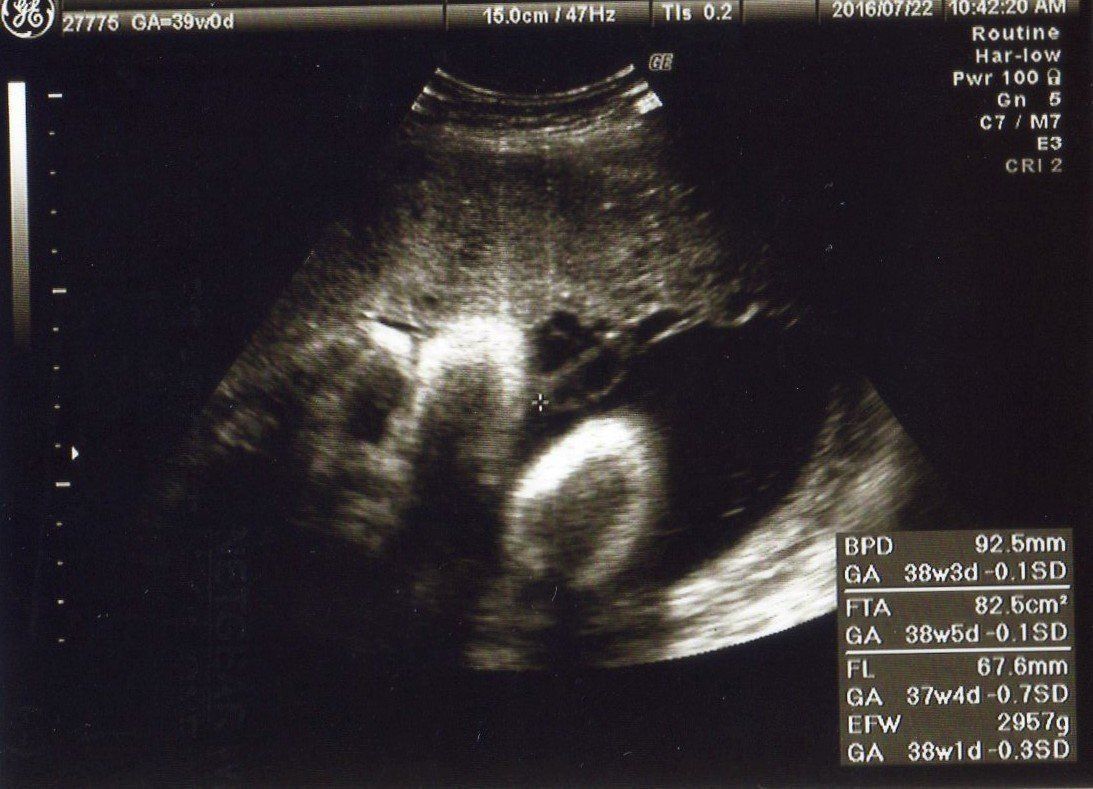

妊娠39週 大きく成長。おなかの中でちょっと窮屈そう

妊娠後期には、週1回通院してNST(ノンストレステスト)のチェックが始まりましたが、毎回赤ちゃんの元気な鼓動を聞くのが楽しみでした。赤ちゃんはますます成長し、頭の大きさは9.2cm、EFW(胎児推定体重)はもうすぐ3000g!

このエコー写真は左から見た横顔です。赤ちゃんは、かわいい姿を見せてくれました。